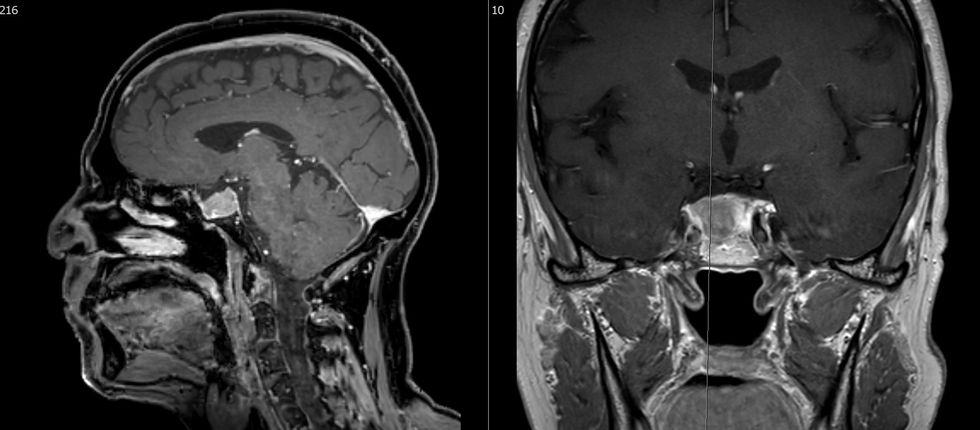

Meningeomat janë tumore intrakraniale që e kanë origjinën nga arachnoidea, pra nga një mbulesë e trurit. Meningeoma zakonisht rritet ngadalë dhe zhvendos strukturat përreth, vetëm 10% tregojnë shenja degjenerimi me rritje të shpejtë dhe infiltrative.

Trajtimi indikohet kur tumoret shkaktojnë simptoma, tregojnë rritje progresive ose shkaktojnë ndryshime në trurin përreth. Heqja kirurgjikale e tumorit është trajtimi primar nëse është lehtësisht i aksesueshëm. Radiokirurgjia (rrezatimi një herë) është një procedurë efektive për tumoret e vogla, të vendosura në mënyrë të pafavorshme ose tumoret reziduale. Përndryshe, ato mund të kontrollohen në intervale të caktuara kohore duke përdorur rezonancë magnetike.

Tumoret e gjëndrës së hipofizës janë zakonisht beninje. Simptomat mund të shkaktohen nga mbiprodhimi ose nënprodhimi i hormoneve ose nga kompresioni lokal në kiazmën optike me humbje të pjesërishme të shikimit ose ngushtim të fushës së shikimit. Tumoret që prodhojnë prolaktinë (prolaktinoma) janë tumoret e vetme që trajtohen në formë medikamentoze, të gjithë tumoret tjerë simptomatik të hipofizës duhet të largohen me operacion. Operacioni kryhet më së shpeshti përmes hundës (transnazal, transfenoidal) në bashkëpunim me kolegët e ORL-së.